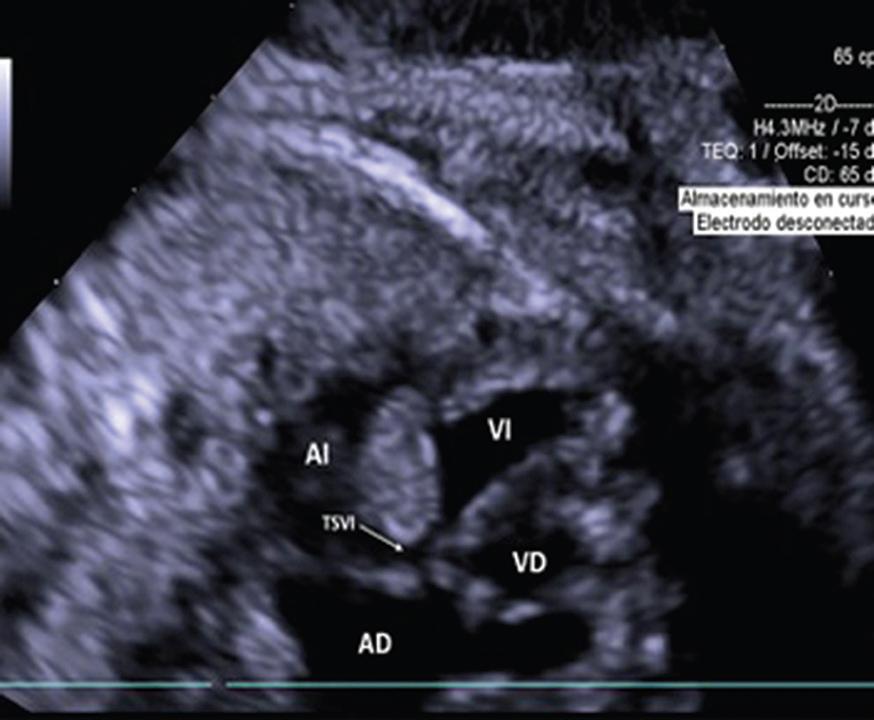

Figura 1 Imagen del ecocardiograma fetal donde se observa en cuatro cámaras 2D imagen de tumor en ventrículo derecho de 20 mm con septum interventricular de 8 mm.

Figura 2 Imagen del ecocardiograma posnatal del mismo paciente, donde se observa en cuatro cámaras 2D tumor en surco atrioventricular de 15.4 x 4.5 mm, en ventrículo derecho con tumor de 17.4 x 22 mm y a nivel del ventrículo izquierdo con múltiples tumores adheridos al septum y a la pared anterior la mayor de 7.7 x 8.2 mm.